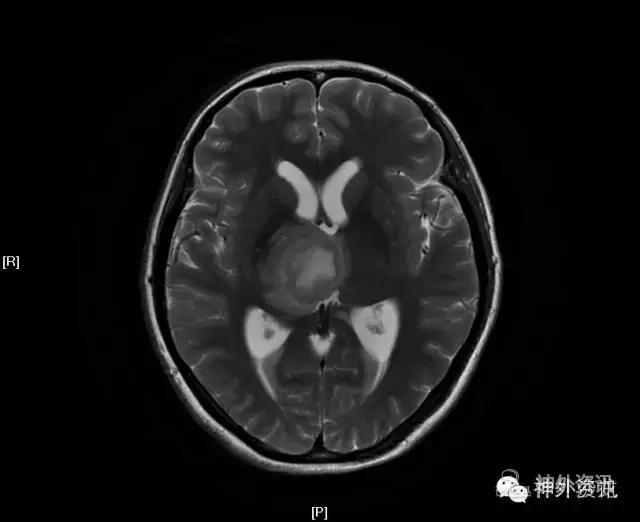

MRI:右侧丘脑占位,考虑胶质瘤可能性大(Ⅲ-Ⅳ级),病灶累及中脑右侧大脑脚,轻度脑积水;不除外转移瘤可能,请结合相关病史及检查。

影像学检查: